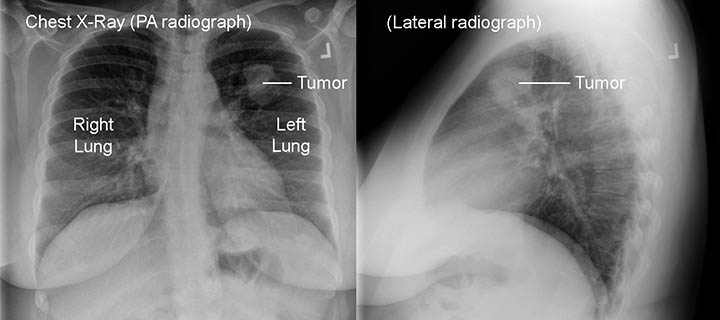

Lung Cancer Screening X Ray

Experience the clarity of Lung Cancer Screening X Ray with our curated collection of comprehensive galleries of images. featuring understated examples of photography, images, and pictures. designed to emphasize clarity and focus. Discover high-resolution Lung Cancer Screening X Ray images optimized for various applications. Suitable for various applications including web design, social media, personal projects, and digital content creation All Lung Cancer Screening X Ray images are available in high resolution with professional-grade quality, optimized for both digital and print applications, and include comprehensive metadata for easy organization and usage. Our Lung Cancer Screening X Ray gallery offers diverse visual resources to bring your ideas to life. Comprehensive tagging systems facilitate quick discovery of relevant Lung Cancer Screening X Ray content. Multiple resolution options ensure optimal performance across different platforms and applications. Time-saving browsing features help users locate ideal Lung Cancer Screening X Ray images quickly. The Lung Cancer Screening X Ray archive serves professionals, educators, and creatives across diverse industries. Instant download capabilities enable immediate access to chosen Lung Cancer Screening X Ray images. Whether for commercial projects or personal use, our Lung Cancer Screening X Ray collection delivers consistent excellence. Professional licensing options accommodate both commercial and educational usage requirements.